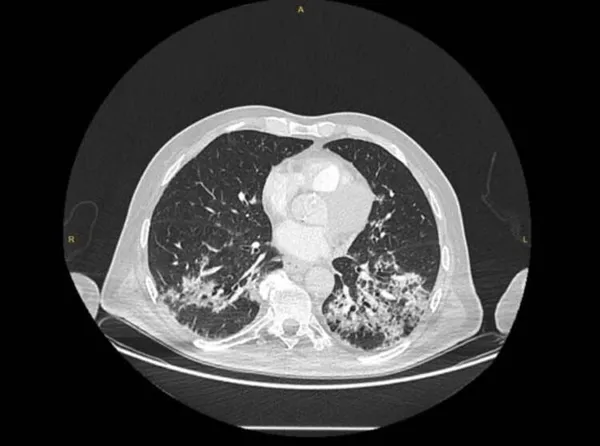

Anadolu Ajansı (AA) Ankara Şehir Hastanesinde Kovid-19 tedavisi gören hastalara ait akciğer görüntülerine ulaştı. Görüntülerde, hastalığın ne kadar hızlı ilerlediği ve akciğerleri nasıl tuttuğu ortaya çıktı.

Prof. Dr. Karalezli, koronavirüs tedavisi gören hastalara ait akciğer görüntülerinden hastalığın yol açtığı tahribatı ve hastalar üzerindeki etkileri anlattı.

Normal akciğer görüntüleri ile koronavirüs hastalarının akciğer görüntüleri arasında ciddi farklar bulunduğunu belirten Karalezli, şu bilgileri verdi:

"İnsanların aradaki farkları anlamaları için her iki akciğer görüntülerine de yer verdim. Görüntülerdeki beyazlıklar akciğerdeki tutulumu gösteren görüntüler ne yazık ki. Bu hastalar yoğun bakım hastaları. Filmler birbirine az çok benzeyen şekilde. Altta yatan hastalığı olanlarda ise daha kötü seyrediyor."

Kliniğe yeni başvuran bir hastanın, 5 Ağustos'ta çekilen tomografi görüntülerindeki tipik koronavirüs görüntülerinin olduğunu ifade eden Karalezli, hastanın bir hafta içerisindeki tomografi görüntüsünde ciddi değişiklik olduğunu ve enfeksiyonun çok arttığını söyledi.